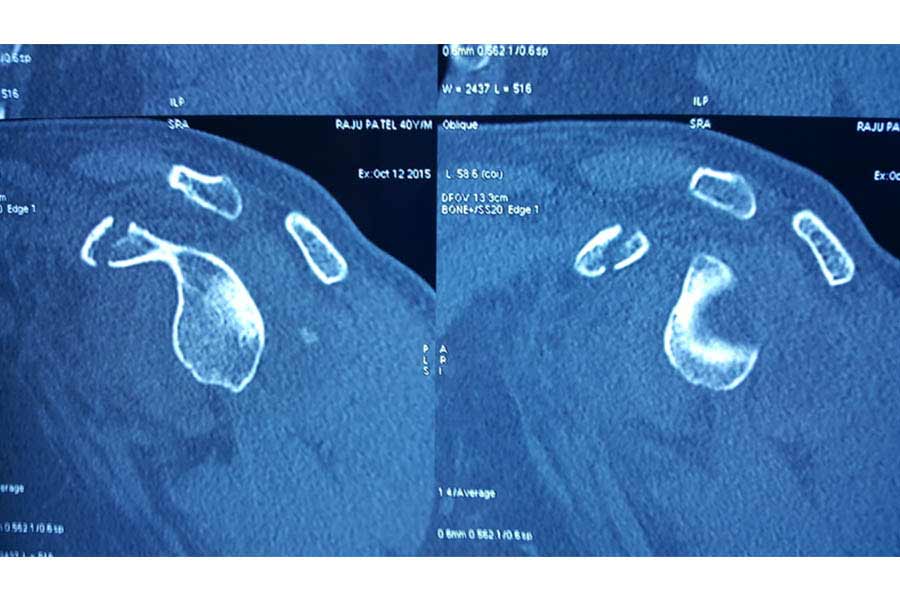

Cold Orthopaedics

Case 1